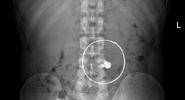

Ежегодно в Склиф поступают десятки пациентов с инородными телами в организме, которым требуется экстренная помощь, а в некоторых случаях — длительное восстановление после хирургического вмешательства.Life.ru